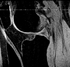

Case 05: Inter-subject knee MRI with different FOV and aliasing:Surface Registration

Case 21: inter-subject knee MRI:Image registration affine+nonrigid